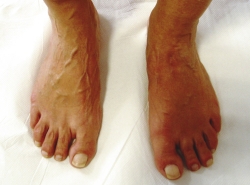

Al realizar la exploración física, se aprecia un ligero abultamiento en el borde interno del mediopié, doloroso sobre todo a la marcha (Figura 1).

Figura 1. Abultamiento en región medial del mediopié.

Se ha realizado una revisión a los 3 años, sigue asintomática y hace vida normal. En el estudio radiológico de control (Figura 7) vemos la consolidación y remodelación ósea y clínicamente la tumoración medial ha desaparecido (Figura 8).

Figura 8. Desaparición de tumoración medial y dorsal.